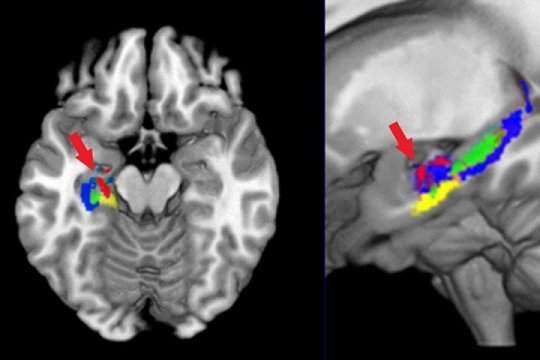

When this method was applied to human participants learning the names and structures of organic compounds, it revealed a decrease in water diffusivity primarily in the CA (Cornu Ammonis) portion of the left hemisphere hippocampus.

The second method made use of the fact that individual concepts have unique representations or neural signatures in the brain that can be identified using functional MRI (fMRI). This approach uses machine learning to detect these representations based on the person’s brain activation pattern. The researchers used this method to identify which of the nine compounds a participant was thinking about, based on the associated brain activation pattern. The researchers found they could identify the neural signatures by looking precisely at that part of the hippocampus where the water molecule motion indicating tissue changes had occurred. The two types of changes occurred in the same 1.3 cubic cm of hippocampus.

A third type of change reflected the development of a brain network that contained the full brain signature of the organic compounds. Not only was the hippocampus involved in these representations, but so were other brain regions, most prominently a region known to support visualization of 3-D structures, the intraparietal sulcus (IPS). The third brain change was an increase in the synchronization of the activity in that very same region of the hippocampus and the IPS, indicating that a network of brain areas showed increased coordination to collectively represent the multiple facets of the concepts.

These three different types of measures — MR (Magnetic Resonance)-diffusion measures of diffusivity change, fMRI measures of the location of the newly acquired concepts and fMRI-based measures of synchronization — showed evidence of microstructural, informational and network change in the left hippocampus during the learning of the organic compounds.